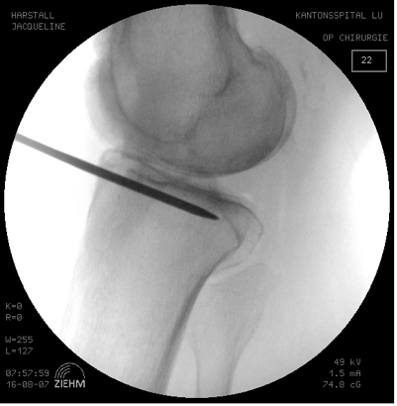

Determination of the osteotomy plane with 2 K-wires.

A first K-wire (3.0) is inserted under image intensifier monitoring from the dorsal superior margin of the pes anserinus to the superior margin of the tibiofibular joint. In order to be able to expose the tibiofibular joint, the knee is brought to 30° IR. The intraosseous length of the K-wire is measured at the same time.

A second K-wire (3.0) is positioned further anterior under image intensifier control so that the two wires are exactly superimposed. This requires that the lateral tibia plateau in the AP image only shows one line. Thus, the osteotomy plane matches the natural tibia slope in the lateral view (Fig. 5a). Thereafter, the length of the two wires is determined (ventrally usually about 10 mm shorter than dorsally).

Placement of parallel K-wires for intraoperative control of the tibial slope and rotation

Now a third K-wire (3.0) is introduced centrally in the proximal tibia with neutral rotation (patella in the center). At the same time, the knee should be flexed under image intensifier control so that the lateral tibia plateau appears as one line. This K-wire now has to appear in the image intensifier as a dot and is thus parallel to the tibial slope (Fig. 5 b).

After predrilling, a fourth K-wire (3.0) is inserted parallel to the third K-wire distal to the osteotomy surface on the anterior tibia (Fig. 5 b). Together with the third K-wire this fourth K-wire permits control of tibial slope and rotation change during the operation.